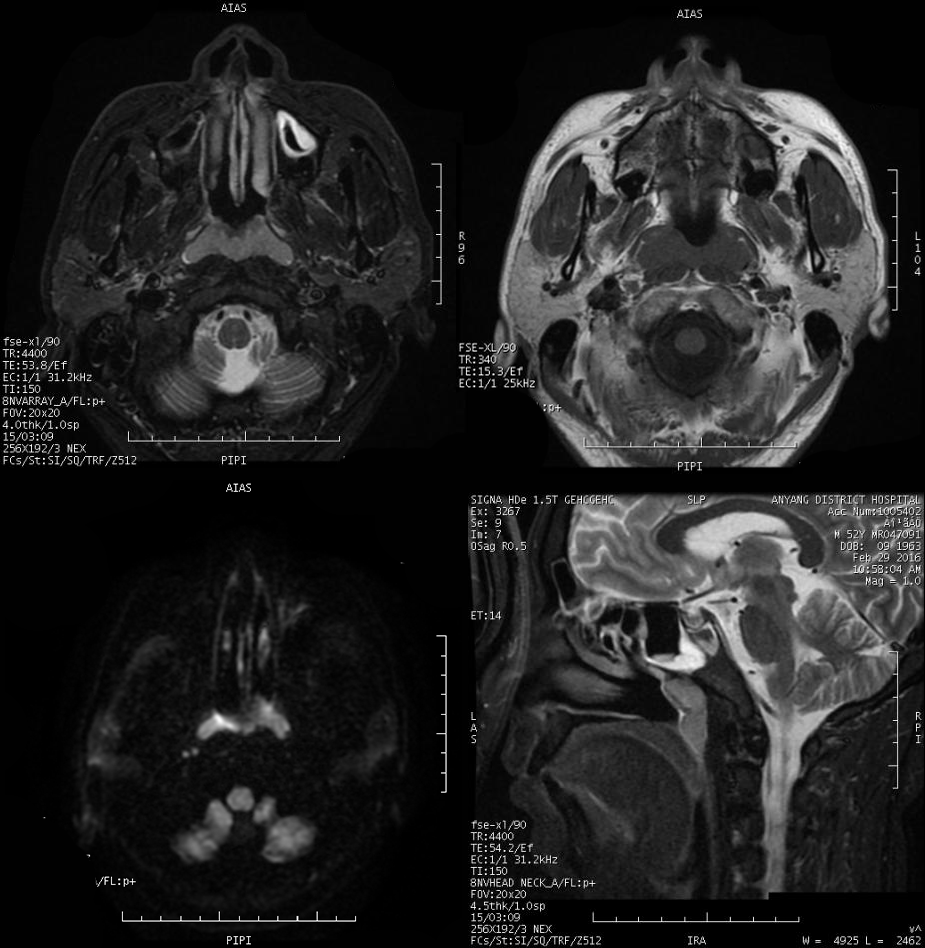

MRI 表现:鼻咽后壁及两侧壁不规则软组织肿块,信号多较均匀,T1WI 像呈等信号,T2WI 像呈稍高信号,DWI 像为明显高信号。增强扫描肿块常轻-中度均匀强化,液化坏死少见。颈部淋巴结肿大常见。肿大淋巴结多边缘规则,内部密度或信号均匀,增强扫描轻度强化。对邻近组织侵犯少,肿块与咽后壁头长肌等分界清楚,多无颅底及相邻骨质破坏。鼻咽部肿块虽较明显,但咽旁间隙较清晰,或只有受压改变。